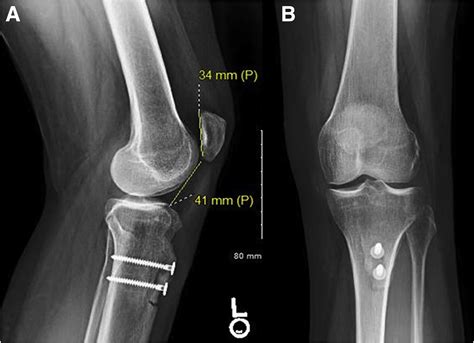

Tibial Tubercle Osteotomy

This surgical procedure involves moving the tibial tubercle, the bony prominence on the shinbone where the patellar tendon attaches, to a new position. By realigning the tibial tubercle, the patella can be repositioned within the trochlear groove, providing better stability and reducing symptoms.